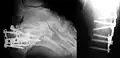

Le calcanéus peut subir des fractures.

Radio d'une fracture du calcanéus.

Radio d'une fracture comminutive du calcanéum